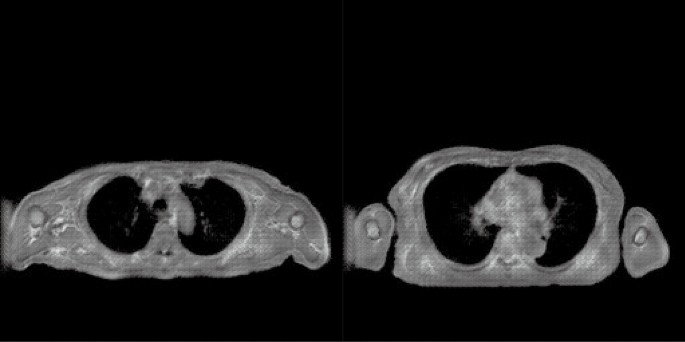

In Figs. 3 and 4, the top images are MRI images, and those in the second to fifth rows are the synthesised CTs. Figures 3b and 4b show the fused images obtained from MRI and synthesised CT. The original ZTE images were synthesised in grey, and the synthesised CT image was in colour. Figures 3c and 4c show cropped images around the humerus in the original MR and fused images obtained from MR and synthesised CT. The displacement between the original ZTE images and the synthesised CT, especially in the body contour and the bone area, is improved by U-GAT-IT + MIND.

Original MR and synthesised CT images along with visual evaluation scores for Patient 1. (a) Original MR and synthesised CT images. (b) Original MR and fused images obtained from MR and synthesised CT. (c) Cropped images around the humerus in the original MR and fused images obtained from MR and synthesised CT.

Original MR and synthesised CT images along with visual evaluation scores for Patient 2. (a) Original MR and synthesised CT images. (b) Original MR and fused images obtained from MR and synthesised CT. (c) Cropped images around the humerus in the original MR and fused images obtained from MR and synthesised CT.